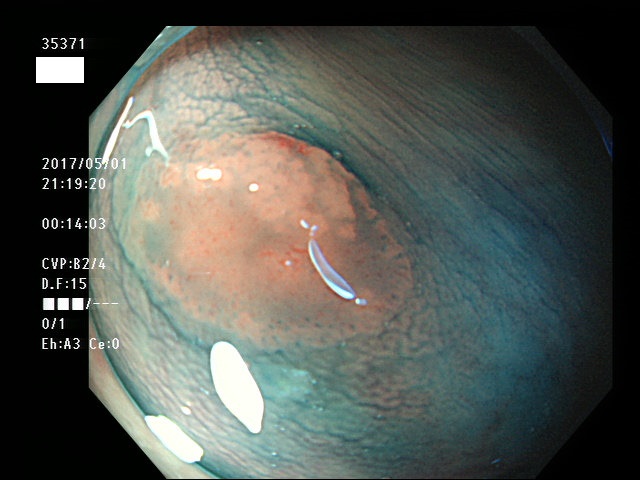

上記100名より抽出した平坦・陥凹型腺腫・SSAP(=癌化の危険が高いが見落としやすい病変)の内視鏡写真